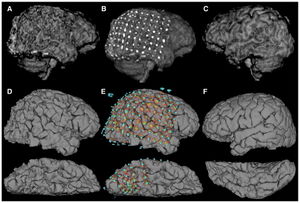

- 5.3 Rapid and Efficient Localization of Depth Electrodes and Cortical Labeling using Free and Open Source Medical Software in Epilepsy Surgery Candidates